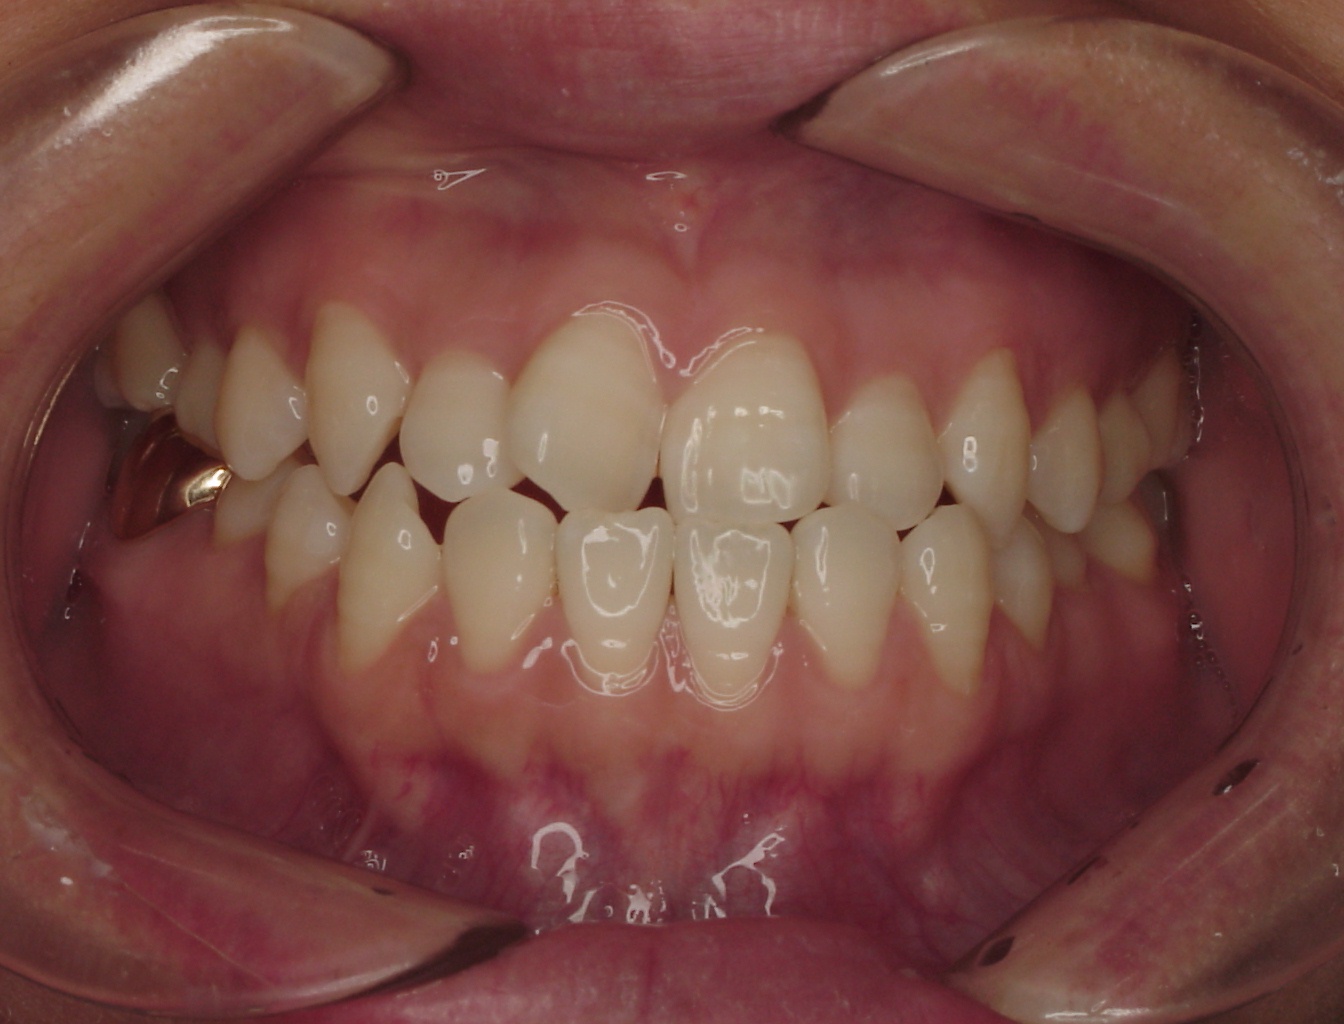

치료 후 사진입니다.